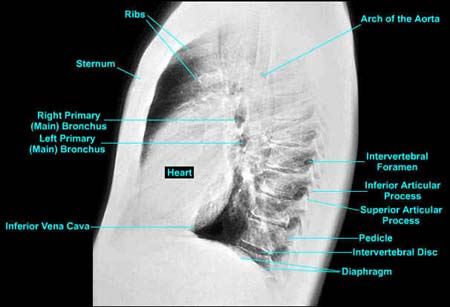

Chest LAT image